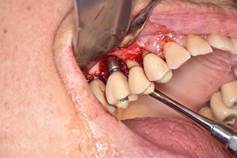

In brief, from the debate held at the peri-implantitis workshop of the First International Congress of Implantology of the School of Dentistry, Universidad de la República, we can conclude that: 1) surgical treatment must always be preceded by non-surgical treatment based on mechanical debridement and the use of antiseptics such as 0.12% chlorhexidine, with a waiting period of three months before starting the surgical treatment (Figs. 8, 9).

Surgical treatment involves: a) opening a mucoperiosteal flap and removing the granulation tissue; b) treating the surface of the implant either with gauze with saline, gauze with 0.2% chlorhexidine, gauze with 3% H2O2, local antibiotics on the implant surface, sodium bicarbonate or glycine spray, Er: YAG laser, mechanical curettage or implantoplasty; c) regenerative or resection techniques; d) systemic antibiotics (amoxicillin 500 mg and metronidazole 500 mg for seven days); e) application of 0.12% chlorhexidine until mechanical hygiene is resumed; f) supportive therapy for three to six months.